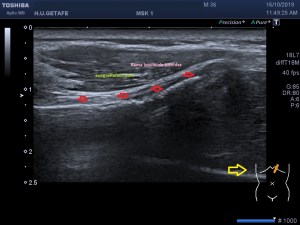

En la imagen 3 ves una imagen de un lipoma, mide 7 cms, la huella de la sonda mide 5cms, la «panoramic view» posee una regla centimetrada que sigue el contorno de la imagen, justo en la profundidad de la misma y lo marca la flecha amarilla. La profundidad la marca la flecha roja y la flecha blanca marca el rango centimetral de los 5cms, fíjate que la línea blanca es ligeramente mayor cada 5 cms. Sirve de referencia, como en la imagen 4 donde ves una colección en el glúteo de más de 10 cms.

Podemos medir valores superiores a los 15cms con alta calidad de imagen…podemos llegar a medir valores por encima de los 25 cms…es verdad que no todos los equipos tienen este ajuste ecográfico, es decir, es una aplicación y por tanto hay que pagarla.